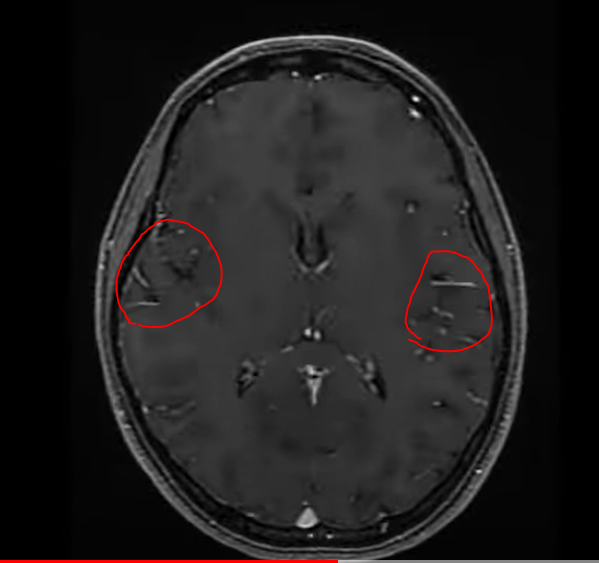

건강검진 mra 사진인데 아직 결과 안나왓고 씨디만 받아온건데 집에서 보다보니 궁금해서요 저 하얗개 지저분한거 원래도 찍으면 나오나요?? 아님 저거 뭐애요?

안녕하세요. 이욱현 의사입니다. 혈관이 찍여서 보인 것으로 보입니다.

이렇게 정상적으로 혈관들이 보입니다. 혈관이 뇌 사이사이를 지나기 때문에 혈관 일부가 보이는 소견으로 보입니다.

혈관 조영제를 사용한 결과입니다. 하얗게 보이는 것은 혈관이 보이는 거에요. 정상인 것이지요.